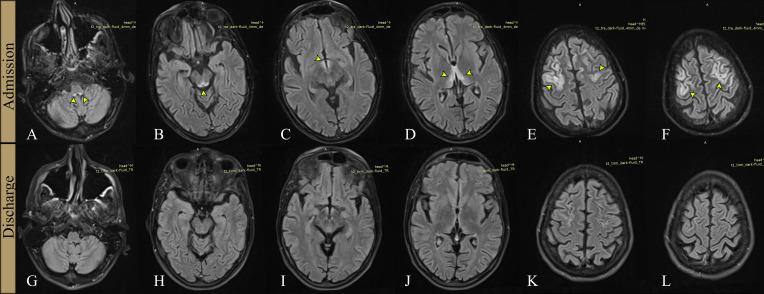

This case involves a young male patient, with a history of chronic alcohol abuse, malnourished, and in poor general health, who presented with right-sided hemiparesis and language disturbance of acute onset, suggesting a left hemispheric stroke. The psychological examination was difficult due to a mix of confusion and aphasia, the latter being challenging to assess as the patient had a dismissive and highly deflective attitude toward the examiner. The initial cerebral computed tomography scan was unremarkable, in line with early imaging in ischemic stroke patients. On subsequent magnetic resonance imaging, lesions were observed in the medullo-pontine tegmentum, around the aqueduct of Sylvius, in the mamillary bodies, in the medial thalami, but also extensive bilateral cortical involvement in the frontal lobes. After receiving intravenous vitamin B1 treatment, the patient made a slow, but full, recovery, after eight weeks of hospitalization, and was subsequently transferred to a psychiatry clinic for treatment of his addiction.

该病例涉及一名年轻男性患者,有慢性酒精滥用史,营养不良,总体健康状况较差,急性起病出现右侧偏瘫和语言障碍,提示左侧半球卒中。由于存在意识模糊和失语的混合情况,心理检查困难,且患者对检查者持轻视和高度回避态度,使得失语难以评估。最初的脑部计算机断层扫描未见异常,这与缺血性卒中患者的早期影像学表现相符。随后的磁共振成像显示,在延髓脑桥被盖部、中脑导水管周围、乳头体、丘脑内侧有病变,同时额叶也有广泛的双侧皮质受累。接受静脉注射维生素B1治疗后,患者在住院八周后缓慢但完全康复,随后转至精神科诊所治疗其成瘾问题。